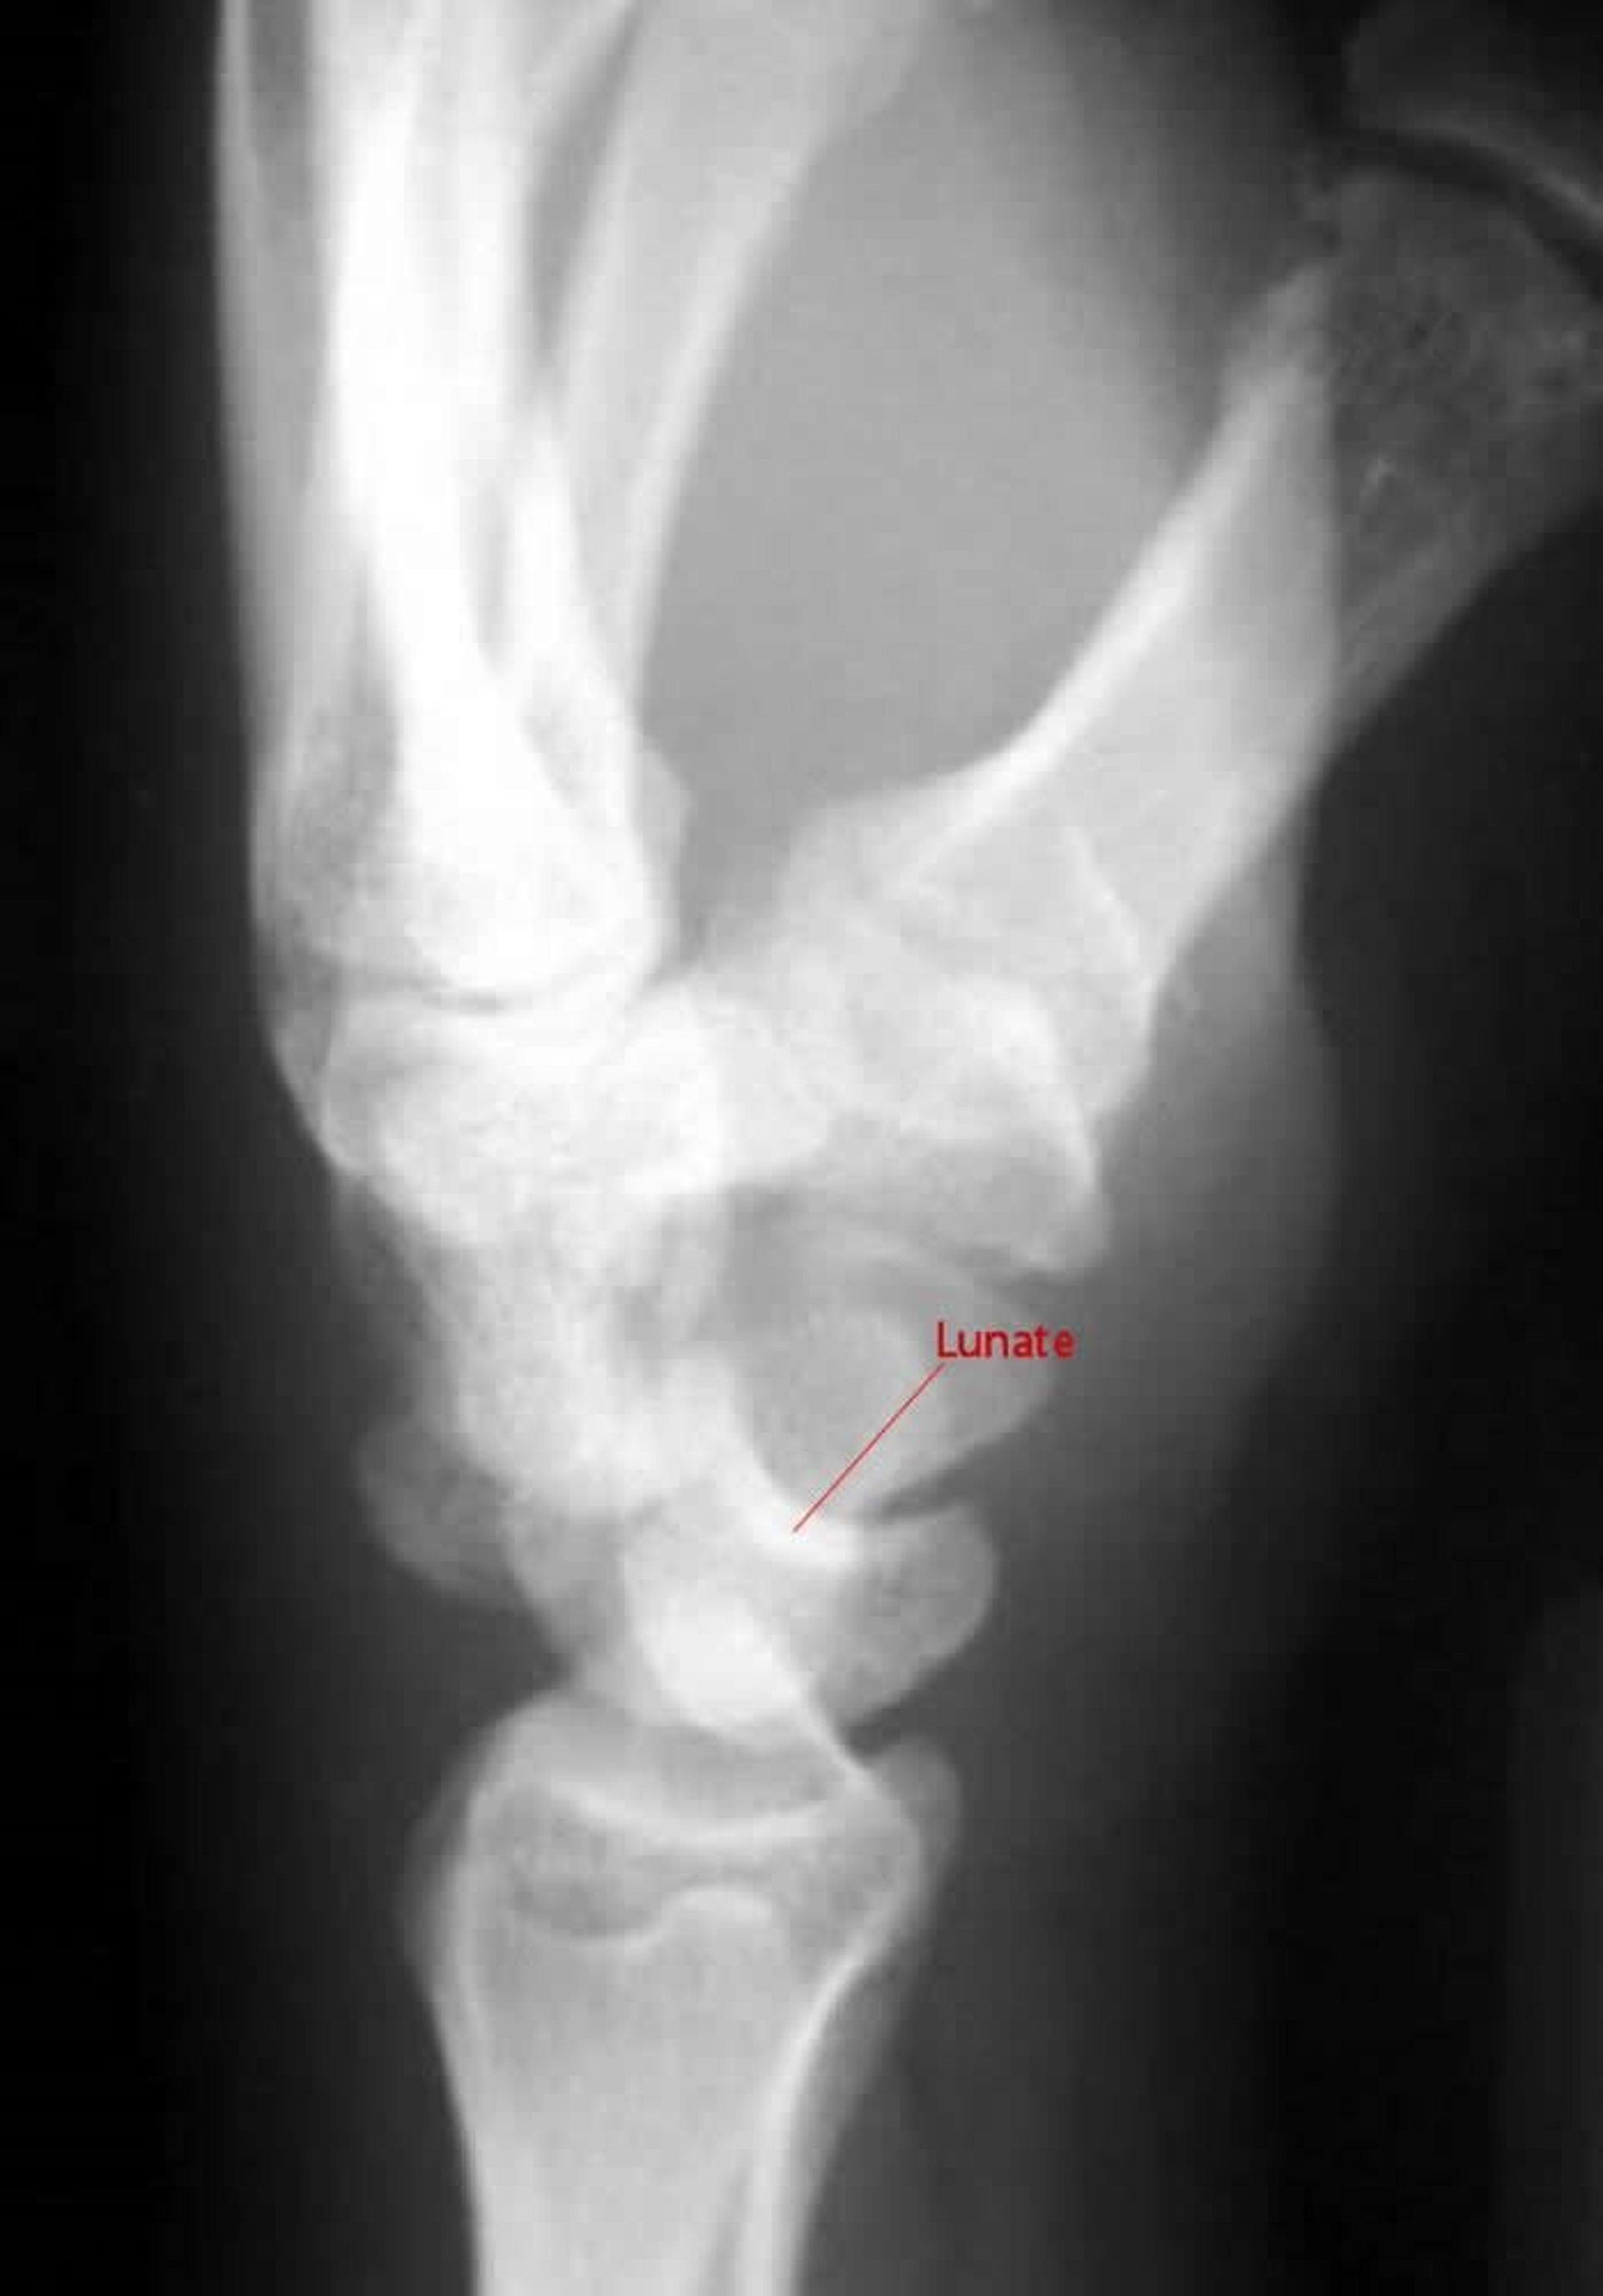

Perilunate Dislocation

On a lateral view of a perilunate dislocation, the capitate does not articulate with the lunate.

Image courtesy of Danielle Campagne, MD.